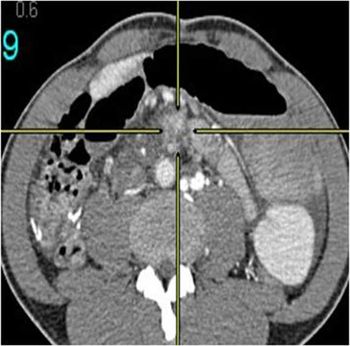

A 17-year-old male patient, no past medical history, presented with two-month history of left groin swelling with gradual increase in size and now pain.